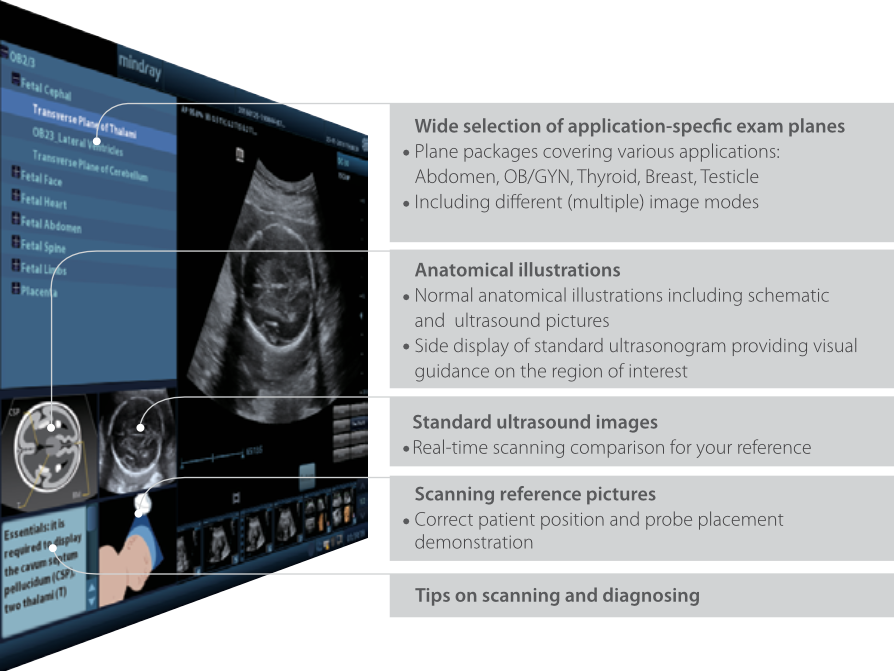

iScanHelper

Speciaal, ingebouwd educatief hulpmiddel dat gebruikers helpt met het 'hoe en wat' van echografie (ultrasound). iScanHelper omvat anatomische illustraties, standaard ultrasoundbeelden, scanreferentiebeelden en tips om vakkundig te scannen.